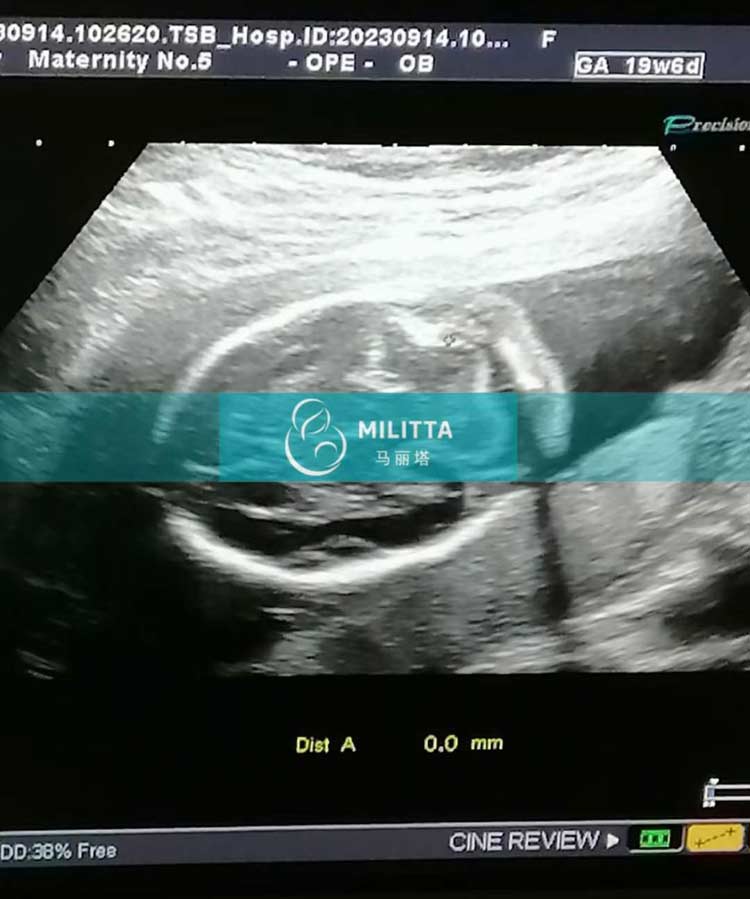

陪同三位乌克兰爱心妈妈来妇产医院做孕检,分别来做19周+B超,18周+B超和抽血常规孕检,检查依然顺利过关,宝宝发育得很好